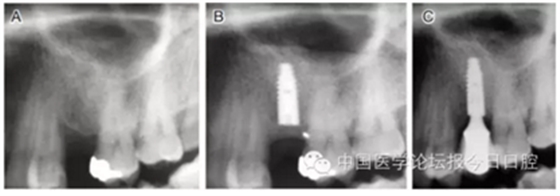

病例1 骨質(zhì)較充裕(圖3)

圖3